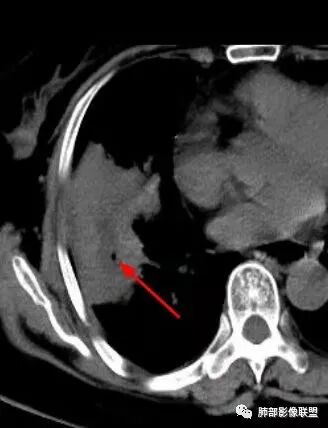

右肺中叶大片实变,内见大片的坏死,中叶外侧段支气管阻塞,相邻胸膜增厚,间隔约四个月后复查,发现低密度坏死内可见气泡影,老年人,反复迁延不愈的病变要考虑恶性,首先考虑腺癌伴感染。鉴别慢性脓肿。

气泡

老年女性,慢性病史,炎性指标稍高,肿标正常,右中下肺大片实变,跨叶生长,边界清,收缩力差,膨隆生长为主,支气管杵状截断,均匀强化,其内坏死边界清,可见悬浮气泡,整体观察,病灶膨隆生长为主,邻近肺野无播散灶,形态单一,尽管慢性病史,影像不支持OP和TB,支气管截断呈杵状,肿标正常,均匀强化,虽是高龄患者,诊断恶性肿瘤有点牵强,综和分析,首选炎性病变放线菌感染,其次考虑低度恶性占位炎机母。

4.坏死腔内壁如何?

南边:跨叶、楔形/边缘平直、支气管壁无破坏/连续/局部无膨大、实变区肺动脉走形自然、实性部分均匀、延迟强化、坏死腔内壁光滑/内壁强化环/近端与支气管相通,这些点均支持炎性。所以综合分析:符合炎性。